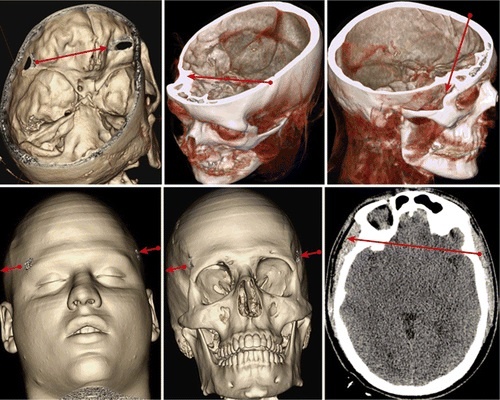

Были ли задеты лобные доли мозга Кутузова, как утверждает статья группы Пройля? Прежде всего, обратим внимание на то, что сделанная исследователями реконструкция первого ранения полководца очевидно неточна. Они отмечают входное отверстие пули в левой части головы сильно за виском, между тем, по реляции Долгорукого, самой близкой к ранению пуля «ударивши между глазу и виска» прошла навылет. Пуля должна была пройти за глазом и перед виском, раздробив кость.

И действительно, на портретах Кутузова, которого, чтобы смягчить вид правого глаза, как правило, изображали в профиль слева, то есть обращенным к зрителю местом входа пули, отчетливо виден шрам и впадина между глазом и виском на месте раздробленной стенки глазницы.

-2

Мы видим этот шрам на гравюре Вендрамини по рисунку Сент-Обена (1813), на портретах Романа Волкова (1814, считается последним прижизненным) и помещенной в Галерее 1812 года в Зимнем дворце  работе Джорджа Доу (1829). Поврежденная стенка глазницы настолько характерный элемент иконографии Кутузова, что проигнорировать его при реконструкции ранения, отнеся входное отверстие к височной кости, – величайшая небрежность. Раздробив стенку глазницы, пуля, особенно небольшая (без экспертизы останков фельдмаршала мы не можем оценить её калибр), вполне могла пройти за глазами, не задев лобных долей мозга и не нанеся фатального урона глазным мышцам и нервам, хоть это и настоящее чудо.

И снова реконструкторы группы Пройля делают произвольное предположение, что пуля вошла в лицо под левым глазом, выйдя ниже затылка. Никаких оснований для такого предположения не дают ни записка Массо, ни изображения Кутузова: никаких шрамов под глазом на них не отмечено. Зато и Волков, и Сен Обен обозначают тенью провалившуюся в результате разрушения части челюсти щеку фельдмаршала. Известные нам прижизненные изображения Кутузова, по возможности щадя оригинал, намечают шрам или провал в центре щеки, чуть ближе к задней её части. Его можно уловить и у Волкова, и у Сент-Обена, еще более явно обозначен шрам на гравюре Готвуда, особенно ясны следы на анонимной немецкой гравюре 1813 года и чрезвычайно нелицеприятной миниатюре Розентреттера.

Пуля вошла в левую щеку не там, где её вход изобразила группа Пройля, не под глазом, а сильно левее и ниже.  Вышла она из шеи.  Мозга, и, тем более, его лобных долей, она задеть не могла. Да и не мог бы Кутузов с раной в том месте, где её изобразили современные «реконструкторы», отдавать приказания егерям и обмениваться колкостями с Де Линем.